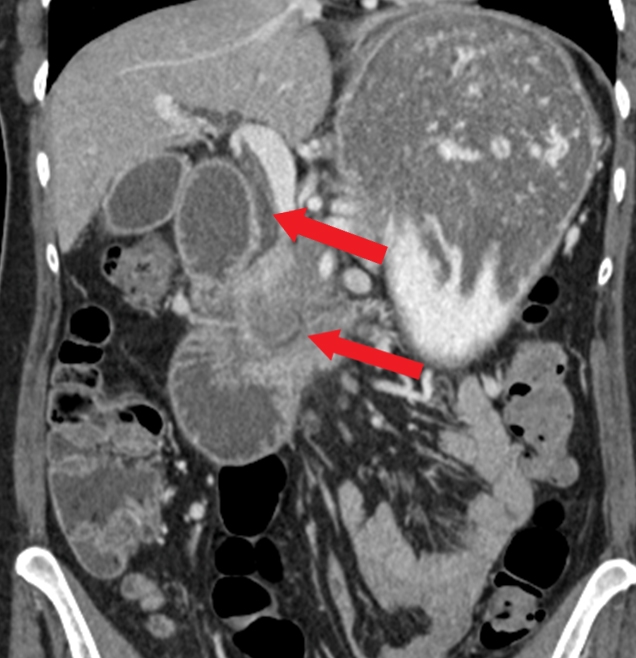

Entamoeba Histolytica

This patient who recently emigrated from Mexico has abdominal pain, fever, leukocytosis, and a liver abscess on imaging. Given his young age, the absence of animal contact, and history of dysentery a few months ago, the most likely etiology is an amebic abscess caused by the intestinal protozoan, Entamoeba histolytica. The differential diagnosis includes pyogenic (bacterial) abscess and hydatid cyst caused by Echinococcus. However, bacterial abscesses generally occur in older patients with underlying medical conditions (eg, diabetes or hepatobiliary disease) or following peritonitis. Echinococcus cysts are not associated with fever, are frequently asymptomatic, and require contact with animals (eg, dogs, sheep); eosinophilia can occur if there is antigenic material leakage.

E histolytica infection (amebiasis) is most common in areas of poor sanitation. Most infected patients are asymptomatic but those with symptoms often develop dysentery. Extraintestinal infection is rare and generally limited to the liver, where the organisms form an abscess. The presentation is similar to a bacterial pyogenic abscess, including fever and right upper quadrant pain. Elevated alkaline phosphatase is common and elevated transaminases may be seen. Imaging typically shows a solitary lesion, generally found in the right lobe of the liver. Serologic testing for E histolytica antibodies confirms the diagnosis. Stool microscopy is insensitive by the time a liver abscess has formed (generally months after the initial infection).

Treatment of amebic liver abscess is with metronidazole (>90% cure with oral therapy). A luminal agent (ie, paromomycin) is also required to eradicate intestinal colonization. Drainage is not recommended routinely due to the high response rate to appropriate antiamebic therapy and the risk of rupture into the peritoneum. Drainage is reserved for mass effect, imminent rupture, or when the diagnosis remains uncertain or the patient is not improving with therapy. In contrast, large hydatid cysts due to Echinococcus can be treated with aspiration in combination with albendazole (Choice C).